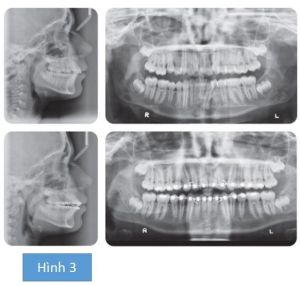

Do bệnh nhân bị chen chúc nhẹ nên bác sĩ quyết định không nhổ răng mà thay vào đó sẽ tạo khoảng bằng cách mài kẽ răng ở nhóm răng trước hàm dưới. Để tạo thuận lợi cho điều này, hệ thống mắc cài tự buộc sẽ được sử dụng. Theo triết lý của hệ thống, việc sử dụng dây Niti lực nhẹ sẽ không thắng được lực mô mềm, bởi vậy tránh nong rộng quá mức 2 cung răng (hình 2). Mặc dù vậy, khoảng được tạo ra chủ yếu để làm thẳng hàng bộ răng chủ yếu là do làm nghiêng ngoài nhóm răng trước (hình 3). Vì điều này vốn không ổn định, đặc biệt là nhóm răng phía trước hàm dưới, nên sau khi tháo niềng, nhóm răng trước hàm dưới sẽ được gắn hàm duy trì cố định, kết hợp với hàm duy trì tháo lắp ở hàm trên và hàm dưới đeo ban đêm. Sau niềng răng, bệnh nhân sẽ được yêu cầu phục hồi R21 không có triệu chứng bệnh lý.